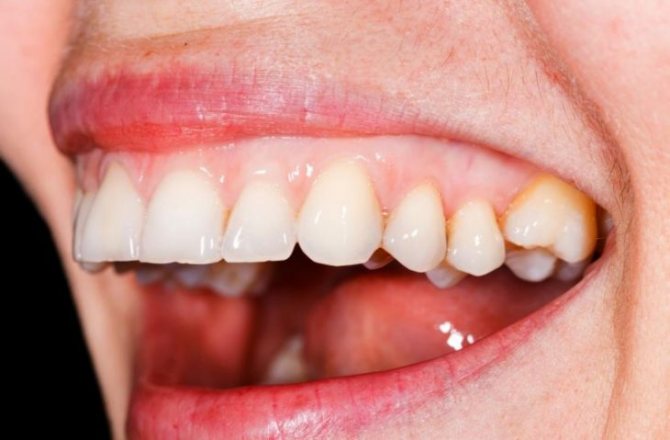

Фото: Волосатая лейкоплакия языка

Фото лейкоплакии